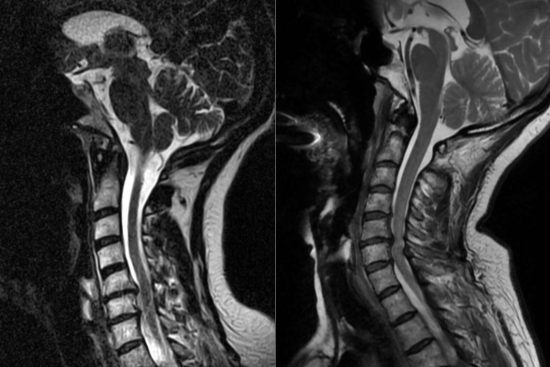

Lo primero es una historia clínica detallada y una exploración neurológica, en la que evaluamos reflejos, fuerza muscular y sensibilidad. Para confirmar el diagnóstico, utilizamos pruebas de imagen como la resonancia magnética, que es la más precisa para detectar hernias y su impacto en las estructuras nerviosas. En casos más complejos, recurrimos a la tomografía computarizada con mielograma o la electromiografía para evaluar el estado de los nervios.